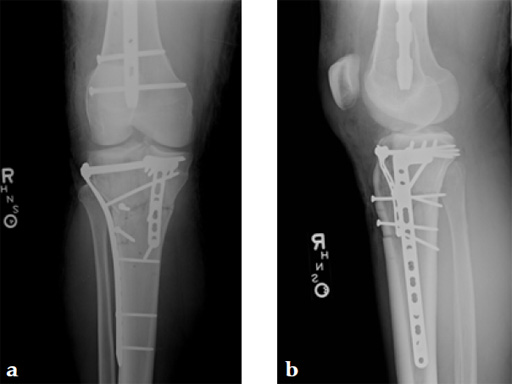

Staged management with initial rodding of femur and placement of spanning knee external fixator with closed manipulative reduction of tibial plateau (Fig 3).

The patient returned to the operating room once soft tissue allowed for open reduction and internal fixation of the tibial plateau fracture via a lateral utility and anteromedial approach. Placement of low bend 3.5 mm proximal tibia plate laterally and 3.5 mm locking T-plate anteromedially to buttress the impacted anterior rim (Fig 4, Fig 5).